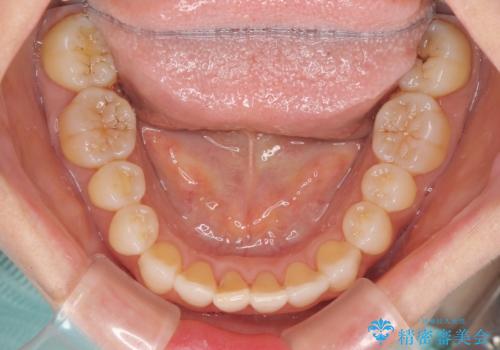

前歯の叢生と切端咬合 インビザラインによる矯正治療

- 前歯のデコボコを気にして来院された患者様です。

上下前歯の先端同士が接触する切端咬合であったため、上顎は歯列を拡大し、下顎はIPR(歯と歯の間を削る)により叢生を解消しながら歯列を小さくすることとしました。

治療前から歯肉退縮が認められ、矯正治療により悪化する可能性が考えられたため、無理のない歯の移動と頻繁な経過観察を行いました。

切端咬合はスムーズに解消され、前歯の負担を軽減させることができました。